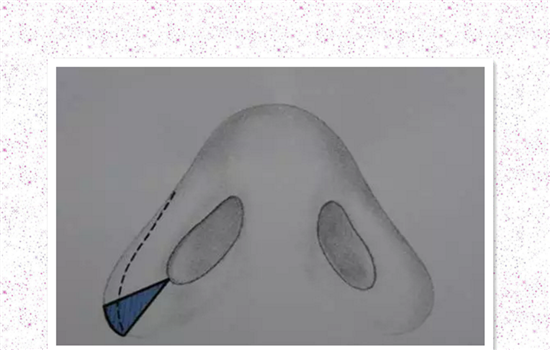

缩鼻翼内切原理图

鼻翼内切主要针对鼻翼的基底部比较宽的求美者,手术在鼻孔内做切口,将鼻翼内收,术后切口痕迹藏在鼻孔内,不容易被发现。鼻翼缩小有外侧切除、内侧切除、外侧和内侧同时切除三种方法,选择哪种方法主要根据鼻翼扩张的情况来决定。

缩鼻翼外切原理图

鼻翼外切针对于鼻翼面积过大的求美者,手术在鼻面沟做切口,切除部分宽大鼻翼软骨 ,切口位置在鼻翼和面颊的界线,愈合后痕迹一样不明显。不过爱美者需要谨记:谨记:鼻子好看与否,是看整体,单纯只做鼻翼缩小,改善效果不明显。

1—单纯鼻翼皮肤侧切除

解决方案:鼻孔大小正常,鼻翼基底较宽,只需要切除鼻翼就可以缩小鼻基底的宽度,并能在保持鼻孔大小的同时改善轮廓。

标记线沿整个鼻翼边缘延伸